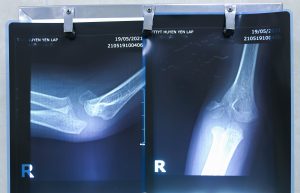

Bệnh nhi Đ.M.Q, 68 tháng tuổi, ở thị trấn Yên Lập, huyện Yên Lập nhập viện vào khoa Ngoại tổng hợp chuyên khoa ngày 19/5/2021 với dấu hiệu đau, hạn chế vận động khuỷu tay phải. Bệnh nhi được chỉ định chụp XQuang, kết quả cho thấy hình ảnh gãy di lệch lồi cầu ngoài xương cánh tay.

Chiều ngày 19/5/2021, cậu bé gan dạ, nhanh nhẹn Đ.M.Q được tiến hành phẫu thuật. Sau khi gây mê, các bác sỹ tiến hành rạch da dọc qua lồi cầu ngoài xương cánh tay, bộc lộ ổ gãy lồi cầu ngoài xương cánh tay, làm sạch 2 đầu xương gãy, nắn lại xương gãy giống như vị trí giải phẫu ban đầu, xuyên 2 kim Kirschner cố định ổ gãy, đóng vết mổ và mang nẹp bột cánh bàn tay.